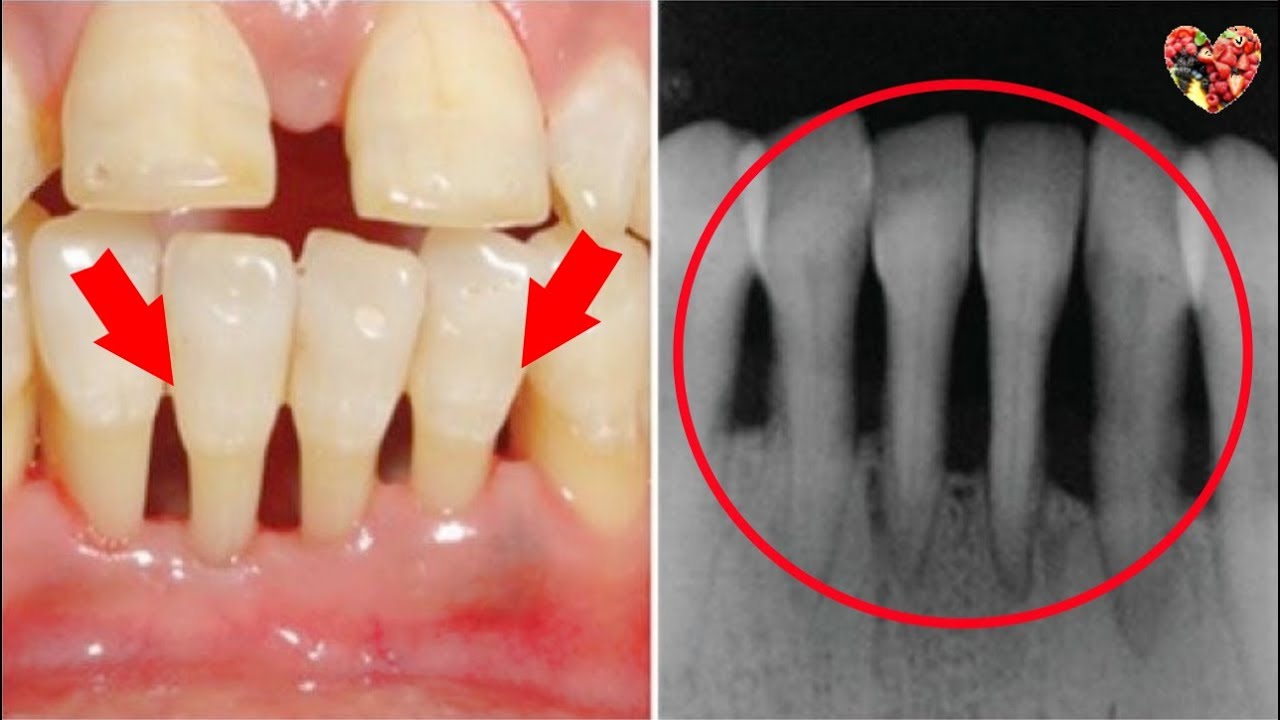

牙齦萎縮是無法自癒的!牙齒會慢慢一顆顆脫落!快用這個方法預防和治療牙齦萎縮!